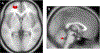

The gut microbiota has recently gained attention as a possible modulator of brain activity. A number of reports suggest that the microbiota may be associated with neuropsychiatric conditions such as major depressive disorder, autism and anxiety. The gut microbiota is thought to influence the brain via vagus nerve signalling, among other possible mechanisms. The insula processes and integrates these vagal signals. To determine if microbiota diversity and structure modulate brain activity, we collected faecal samples and examined insular function using resting state functional connectivity (RSFC). Thirty healthy participants (non-smokers, tobacco smokers and electronic cigarette users, n = 10 each) were studied. We found that the RSFC between the insula and several regions (frontal pole left, lateral occipital cortex right, lingual gyrus right and cerebellum 4, 5 and vermis 9) were associated with bacterial microbiota diversity and structure. In addition, two specific bacteria genera, Prevotella and Bacteroides, were specifically different in tobacco smokers and also associated with insular connectivity. In conclusion, we show that insular connectivity is associated with microbiome diversity, structure and at least two specific bateria genera. Furthemore, this association is potentially modulated by tobacco smoking, although the sample sizes for the different smoking groups were small and this result needs validation in a larger cohort. While replication is necessary, the microbiota is a readily accessible therapeutic target for modulating insular connectivity, which has previously been shown to be abnormal in anxiety and tobacco use disorders.